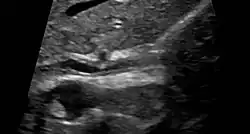

| Cholangiogram of primary sclerosing cholangitis | |

Historically, a cholangiogram would be obtained via endoscopic retrograde cholangiopancreatography (ERCP), which typically reveals "beading" (alternating strictures and dilation) of the bile ducts inside and/or outside the liver. Currently, the preferred option for diagnostic cholangiography, given its noninvasive yet highly accurate nature, is magnetic resonance cholangiopancreatography (MRCP), a magnetic resonance imaging technique. MRCP has unique strengths, including high spatial resolution, and can even be used to visualize the biliary tract of small animal models of PSC.[22]